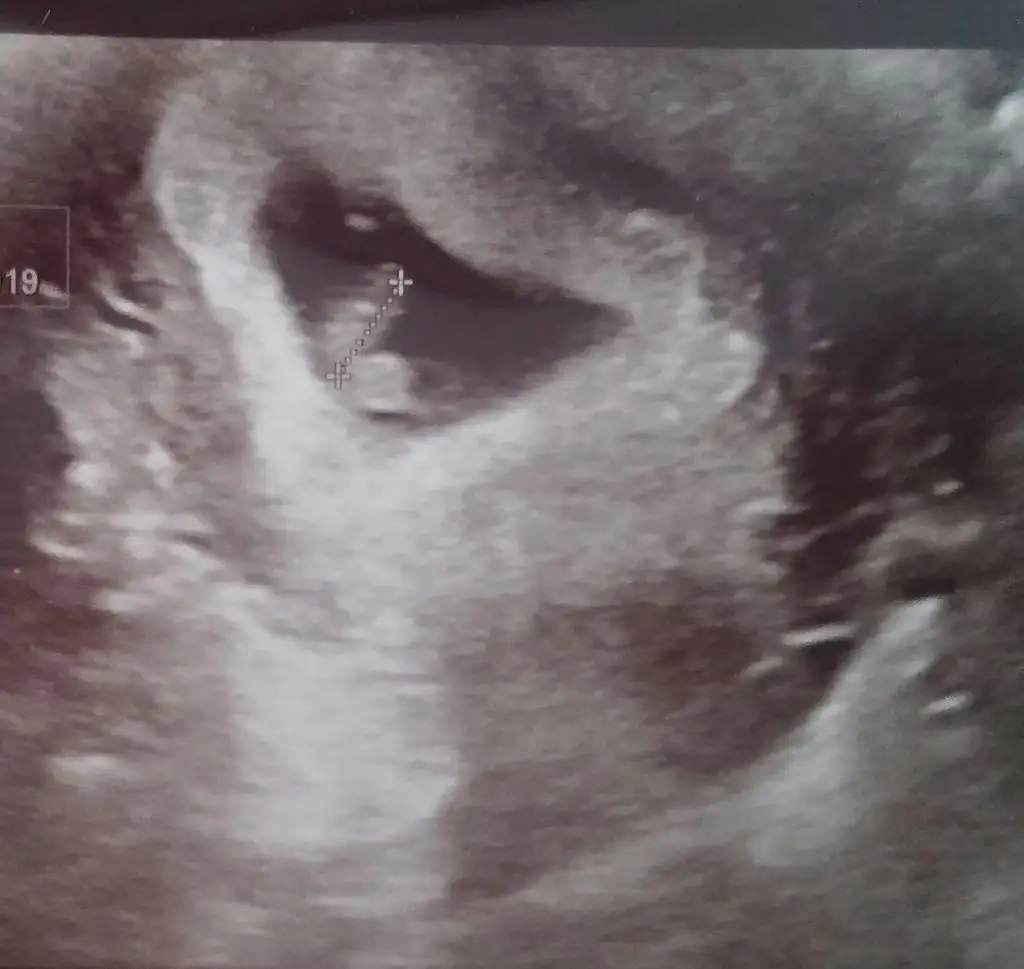

Sağlıkla ilerlesin inşallah canım . Maşallah bebişe :)